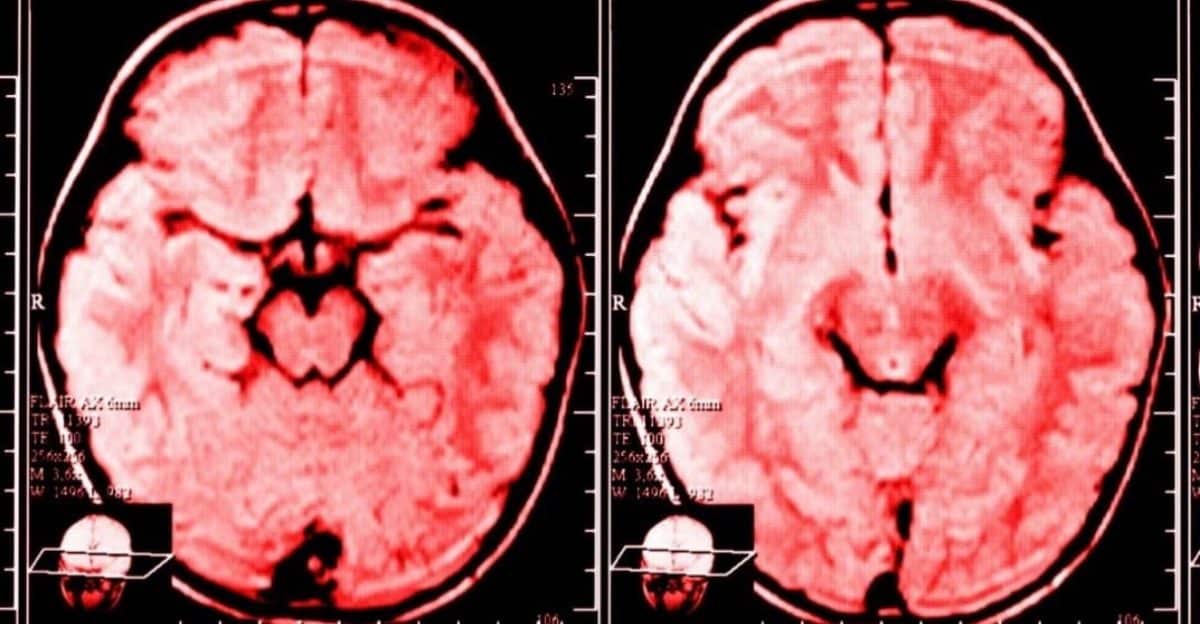

Nos últimos 20 anos, graças ao rápido desenvolvimento nas esferas da imagem cerebral e da neurociência, podemos agora dizer com certeza que o cérebro é capaz de fazer reengenharia em si mesmo.

De muitas maneiras, a ‘neuroplasticidade’ – um termo genérico que descreve a mudança duradoura no cérebro ao longo da vida de uma pessoa – é uma área fascinante da ciência.